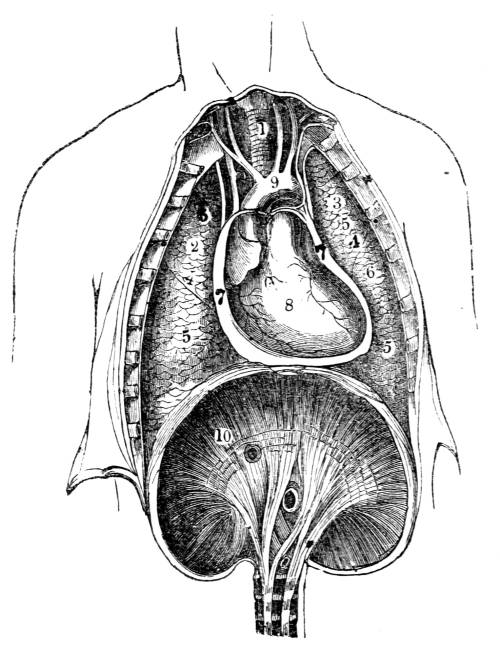

Fig. CXXXIV.—

View of the Respiratory Apparatus in

Man.

1. The Trachea. 2. The right lung. 3. The left lung.

4. Fissures, dividing each lung into, 5. Large portions

termed lobes. 6. Smaller divisions termed lobules. 7.

Pericardium. 8. Heart. 9. Aorta. 10. Diaphragm separating

the cavity of the thorax from that of the abdomen.

357. In man there are two pulmonary bags (fig.

CXXXIV. 2, 3), of nearly equal size, which, together

with the heart, completely fill the large cavity

of the thorax (fig. CXXXIV.), their external surface

being everywhere in immediate contact with

the thoracic walls. One of these bags is placed on

the right side of the body, constituting the right

lung (fig. CXXXIV. 2), and the other on the left,

constituting the left lung (fig. CXXXIV. 3). Each

lung is divided by deep fissures, into large portions

called lobes (figs. CXXXIV. 4, and CXXXV.

6), of which there are three belonging to the

right, and two to the left lung. Each lobe is

subdivided into innumerable smaller parts termed

lobules (figs. CXXXIV. 6, and CXXXV. 6), while the

lobules successively diminish in size until they

terminate in minute vesicles that constitute the

great bulk of the organ (fig. CXXXV. 8).